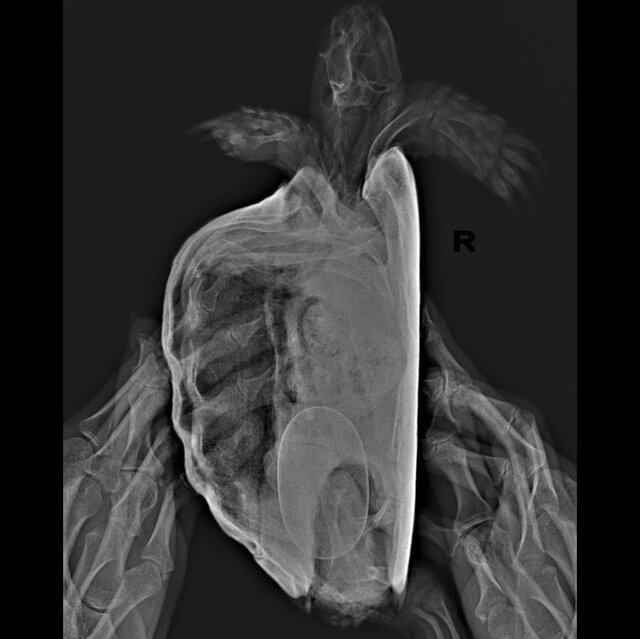

Если кратко, за последние несколько лет мне отдали знакомые люди две черепахи. Я стала за ними ухаживать, любить и растить, купила террариум, лампы, набираю сено на зиму на подстилку, летом гуляют в вольере на улице. В общем оказалось, что они разнополые, когда только появлялась каждая из них я не смогла различить, потому что были похожи. Но когда они стали половозрелые, я подумала может у них что-то получится и это случилось в этом году. На ренгене (30.09.2023) я узнала, что у девочки одно яйцо и она начала проявлять беспокойство, отказывалась от еды и закапывалась в подстилку. В клинике сказали ждать, у них не было такого опыта с беременными сухопутными черепахами. Я начала искать информацию в интернете, смотреть видео и вроде бы всё окей она сама прекрасно справится. Но сегодня 27 октября, я уже с нейросетью искала информацию, очень переживаю и уже готова пойти в ветклинику и последовать совету лопнуть и вытащить яйцо, как это делают попугаям с проблемой откладки. У меня нет в городе больше специалистов в принципе по черепахам. Есть ли тут ветврачи или люди с опытом, что может помочь определить проблему? Или всё нормально и стоит бить тревогу, если она и за ноябрь не отложит яйцо?

Клоака увеличилась за последние пару дней, отверстие будто стало больше и она стала часто тужиться, мне предлагали немного вазелином смазывать, так я заметила, что яйцо ушло глубже, потому что оно было почти у отверстия. Сказали прививки не надо, потому что витамины делали в июле, яйцо очень твердое и кальция нормально в организме. Может у неё яйцо не в правильном положении? Вот прилагаю ренген. Если всё серьезно я поеду в Москву, если вариант, что в ветклинике как попугаю вытащат яйцо - хорошо я так и сделаю. Я купаю раз в неделю в тазике черепаху, оставляю в теплой воде, аппетит хороший и пьет из миски воду сама. Но тужится, и так весь месяц по нарастающей, я боюсь, что это долго

Девочка, среднеазиатская черепаха, больше 10 лет, вес 704гр

врач ответила, что яйцо крупное, но должно быть всё хорошо. Но если будет видно, что яйцо стоит в клоаке и ни туда ни сюда - да, можно как с птицами, вагинальным зеркалом расширить клоаку, асперировать содержимое яйца иглой и пинцетом вытащить скорлупу. Но это должен делать тот, кто понимает что делает.